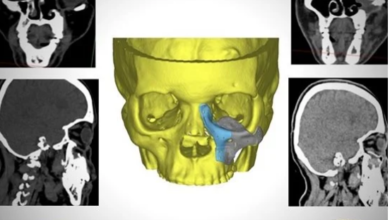

معجزة طبية.. هيئة الرعاية بالأقصر تعيد بناء عظام الوجه لسيدة أصيبت بالفطر الأسود

استطاعت الهيئة العامة للرعاية الصحية بالأقصر من خلال قسم جراحة الوجه والفكين وأورام الرقبة بمستشفى الكرنك الدولي من إعادة بناء…